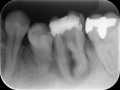

歯肉貫通部の形は正中を中心にシンメトリックが望ましく、歯と歯の間の尖った三角形の歯肉も美しく獲得できていること。そして、長期的に骨と歯肉をキープするには咬合によるストレスが全体にバランスよくかかることが大切で、その為には正しい位置にインプラントが埋入されていることが絶対的な条件であります。骨のない歯肉部分を貫通するアバットメントは透けてみえたとしても問題の無いように歯と同じ色を使用することがあります。ジルコニアという強度も審美性も十分な素材を使用したアバットメントを使用し、オールセラミック製の上部構造をセット。あとは馴染むのを待ちます。写真は装着直後と3か月後を撮影したものです。